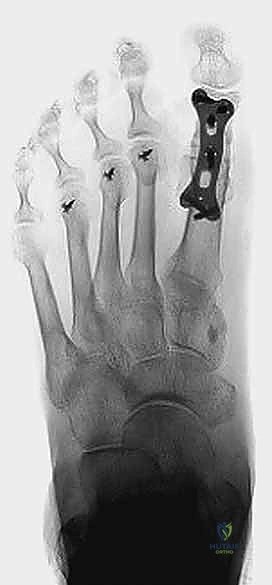

جراحة تثبيت مفصل إبهام القدم الكبير المراجعة: استعادة الوظيفة وتخفيف الألم مع الأستاذ الدكتور محمد هطيف

هل تعاني من ألم مستمر بعد جراحة سابقة لإبهام القدم؟ تعرف على جراحة تثبيت مفصل إبهام القدم الكبير المراجعة، حل فعال لاستعادة الوظيفة وتخفيف …

تثبيت مفصل إبهام القدم الكبير: الحل الجراحي المتقدم لإبهام القدم المتصلب مع الأستاذ الدكتور محمد هطيف

تعرف على عملية تثبيت مفصل إبهام القدم الكبير (MTP) لعلاج إبهام القدم المتصلب المتقدم. يقدم الأستاذ الدكتور محمد هطيف في صنعاء أحدث التقنيات…